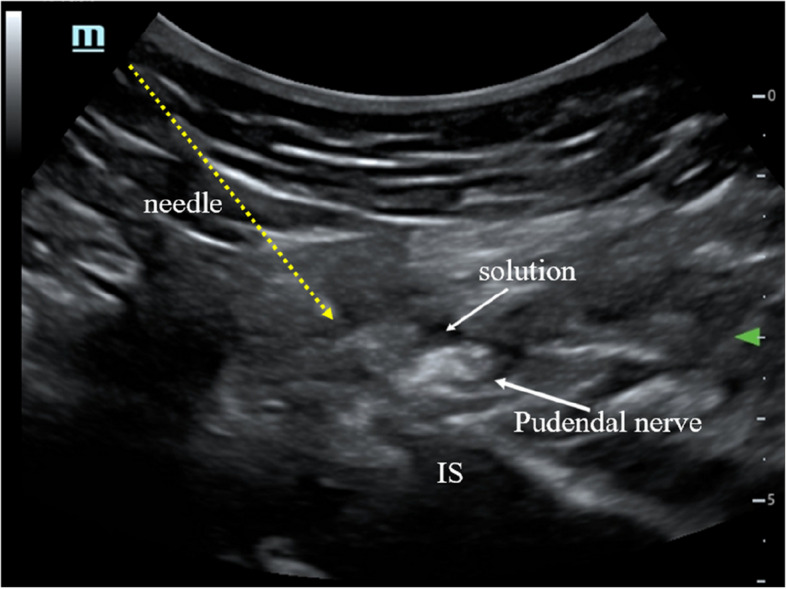

The patients will be in a prone position. First, an ultrasound transducer will be positioned at a transverse plane to visualize the ischium forming the lateral border of the sciatic notch. When the probe is moved in the cephalad–caudal direction, the length of the ischium gradually increases, with the widest point at the level of the ischial spine. The ischial spine will be identified by visualizing the internal pudendal artery again. Thereafter, a local anesthesia compound (2% lidocaine 1.5 ml + 1% ropivacaine 1.5 ml + 0.9% NaCl 2 ml) will be administered to the medial aspect of the internal pudendal artery (Fig. 3).

Fig. 3.

Pudendal nerve block or PRF treatment. IS, ischial spine

Pudendal nerve PRF

The patients will be placed in a prone position. Under ultrasound guidance, the puncture needle will be inserted near the pudendal nerve (Fig. 3). After connecting the electrode and PRF needle, sensory stimulation at a frequency of 50 Hz, pulse width of 1 ms, and voltage of 0.3–0.5 V will be administered to produce paresthesia in the innervation of the pudendal nerve. PRF will be administered at 42℃ for 480 s. Thereafter, a 5-ml nerve nutrition compound (2 ml of 2% lidocaine + 1 ml of 0.5 mg mecobalamin + 1 ml diprospan + 1 ml of 0.9% NaCl) will be injected.